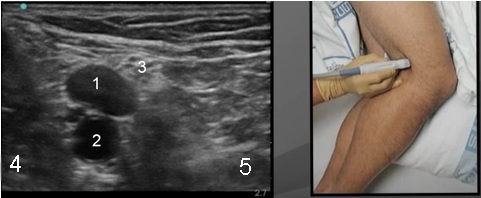

Popliteal 1 Graphic and Image

Tibial Nerve

Popliteal Vein

Popliteal Artery

Lateral

Medial